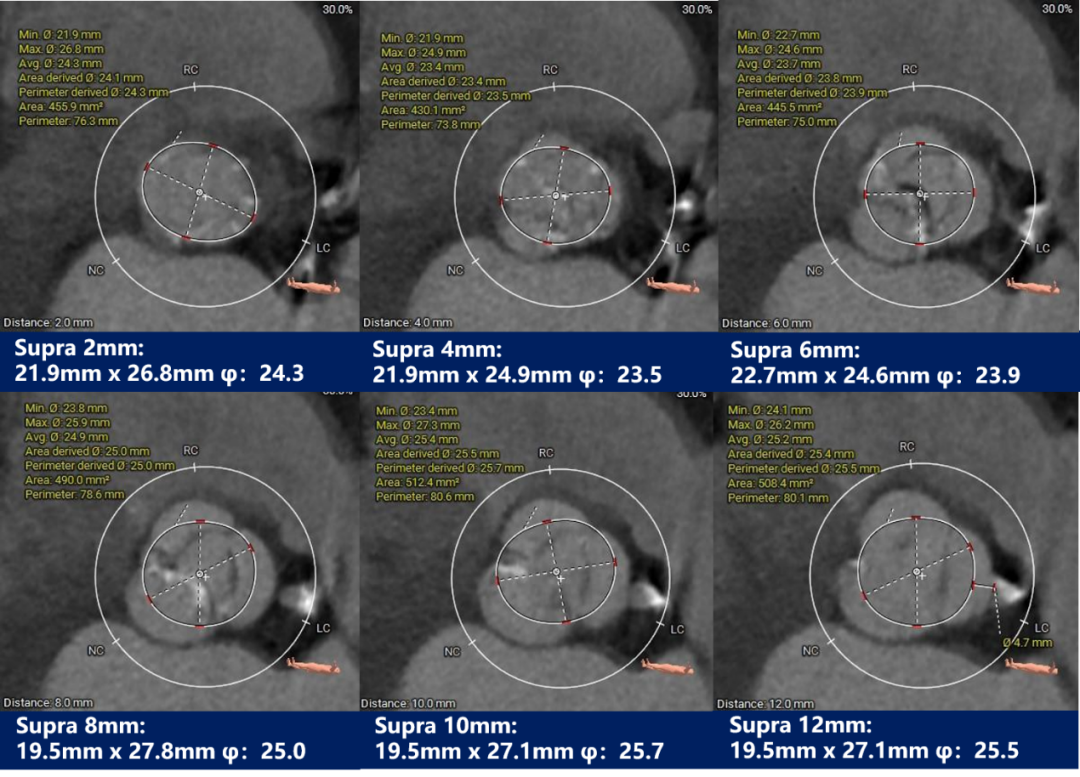

瓣上测量:

瓣上测量:瓣叶中度钙化,钙化分布不均匀,主要分布于右无交界融合处,且无窦下钙化延伸至LVOT。